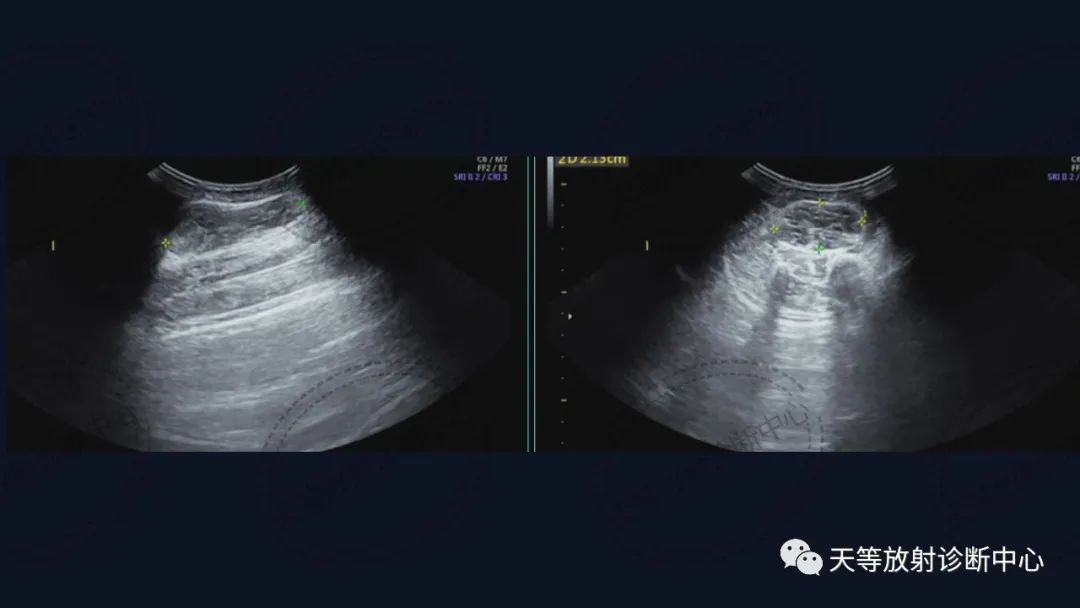

上图:压脂序列肿块椭圆形,内部见细小分隔,血管流空信号。

组织学上主要表现为血管管道数目的增加及纤维结缔组织、平滑肌、炎性细胞和毛细血管、淋巴管等不同程度的浸润。MRI观察病灶内纤维结缔组织呈分隔状及线状低信号影,含血管成分可表现血管流空信号影。病灶内出血表现信号混杂等。